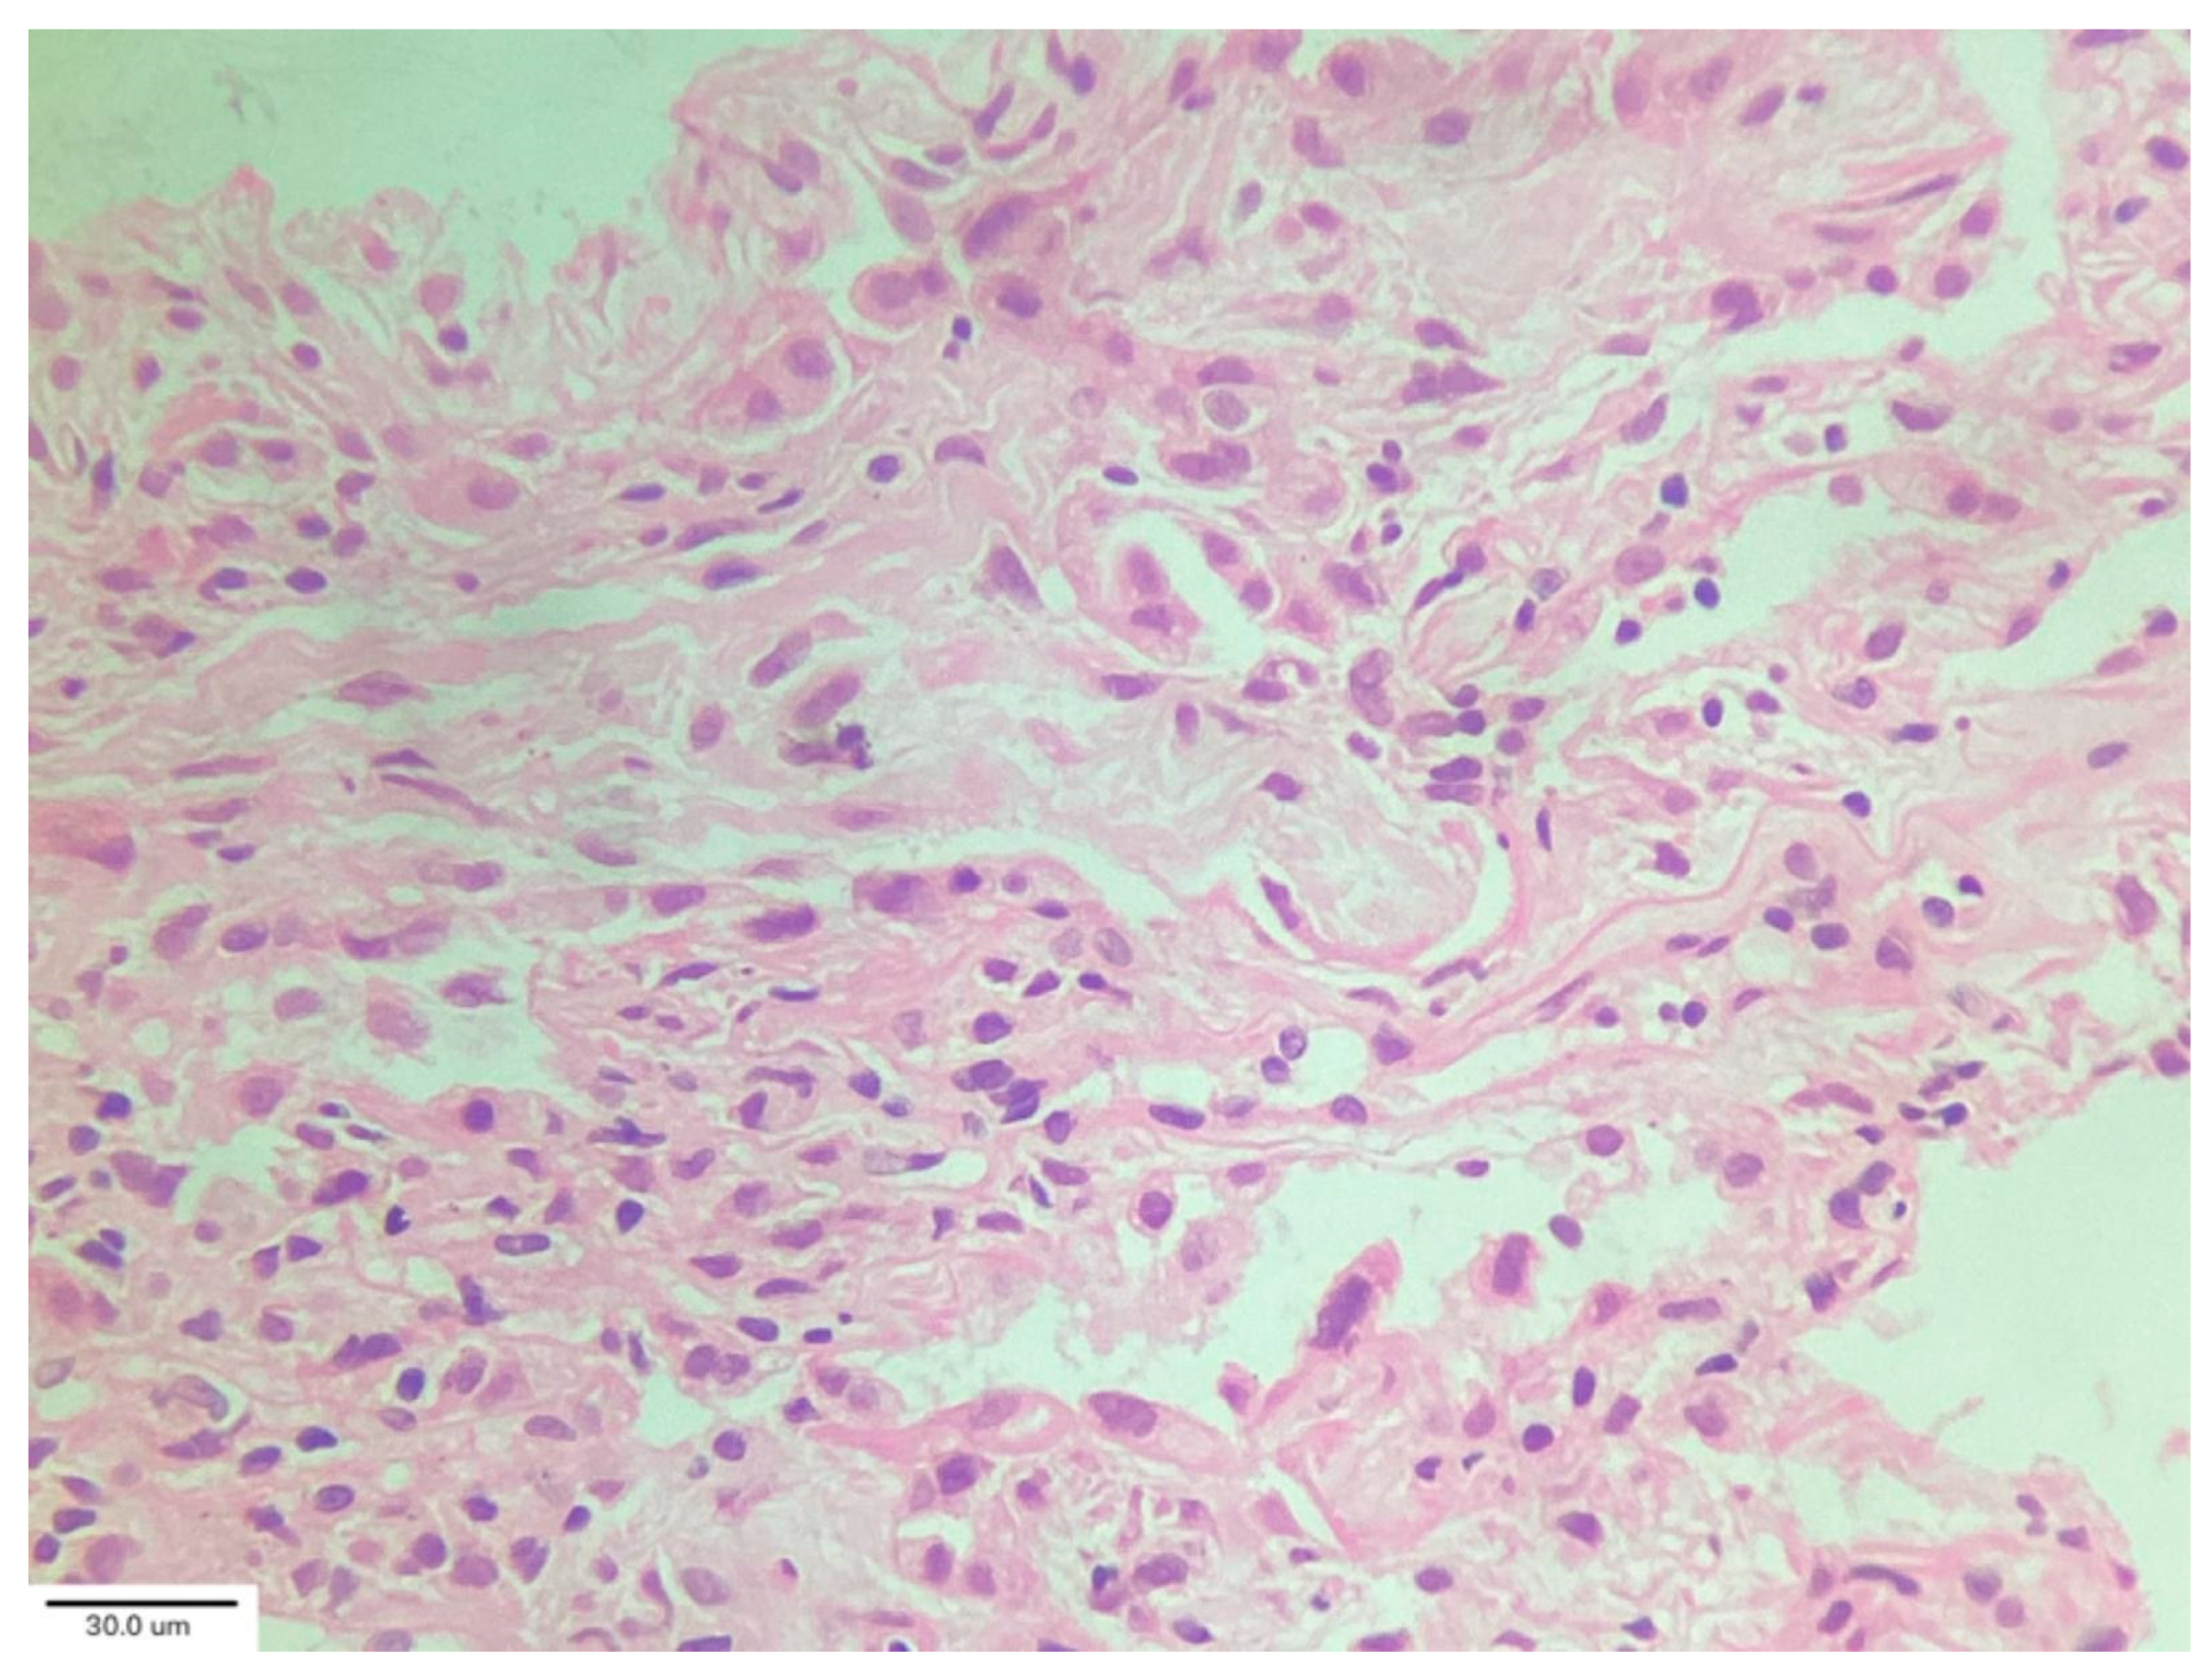

In their analysis of cryobiopsies in post-COVID-19 patients, Culebras et al. [34] described the following findings: OP with Masson bodies (Figure 6), varying degrees of lymphoplasmacytic interstitial infiltrates and interstitial giant cells, and patchy collagenous interstitial/alveolar scars in the absence of fibroblastic foci. The fibrosis was confined in shape and distribution to “old OP.” No clear irreversible fibrosis or any classic pattern (UIP or NSIP) or smoking-related interstitial fibrosis, was observed. There were no hyaline membranes, fibroblastic enlargement of the interstitium, or thrombi observed in these biopsies. The most common injury pattern encountered on histologic analysis of postmortem and explant biopsies after COVID-19 is diffuse alveolar damage (DAD), the histologic correlate of ARDS. ARDS, both of infectious and non-infectious origin, may progress to the development of significant and irreversible pulmonary fibrosis [35].

Figure 6. Organizing pneumonia with Masson bodies (arrow) and varying degrees of lymphoplasmacytic interstitial infiltrate. Magnification: H&E ×40.